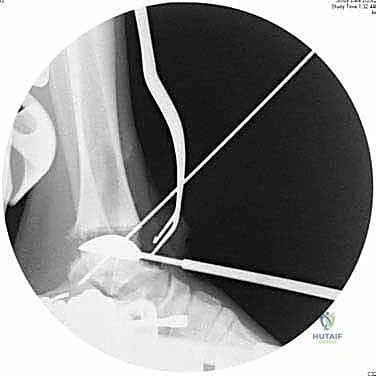

6. التحقق والإغلاق

يتم فحص المدى الحركي للكاحل الجديد وثباته تحت جهاز الأشعة السينية (Fluoroscopy) داخل غرفة العمليات للتأكد من المحاذاة المثالية بنسبة 100%. بعد ذلك، يتم إغلاق الشق الجراحي بغرز تجميلية، ووضع جبيرة ناعمة أو حذاء طبي واقٍ.